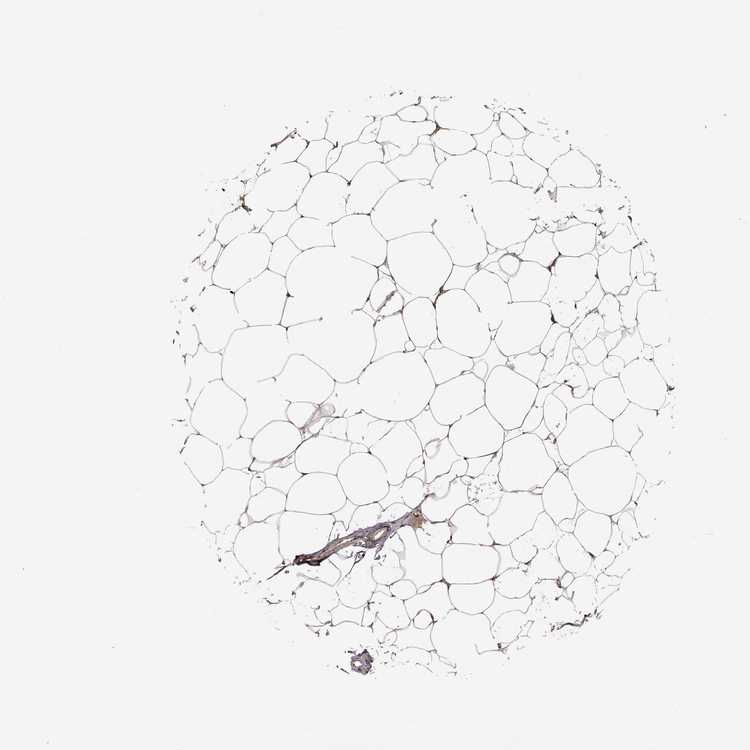

BREAST - Antibody stainingi

Antibody staining in the annotated cell types in the current human tissue is reported as not detected, low, medium, or high, based on conventional immunohistochemistry profiling in selected tissues. This score is based on the combination of the staining intensity and fraction of stained cells.

Each image is clickable and will lead to virtual microscopy that enables deeper exploration of all samples and also displays staining intensity scores, fraction scores and subcellular localization as well as patient and tissue information for each sample.

Antibody HPA072244

Adipocytes Medium

Glandular cells Medium

Myoepithelial cells Not detected